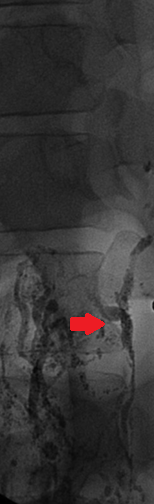

Ένας 46χρονος ασθενής , με μακροχρόνιο πρόβλημα γαστρο-οισοφαγικής παλινδρόμησης , ανθεκτικής στην συντηρητική θεραπεία , υποβλήθηκε σε λαπαροσκοπική θολοπτύχωση κατά Nissen , σε άλλο νοσοκομείο της πόλης μας . Κατά δήλωση του , η όλη διαδικασία εξελίχθηκε ομαλά και έλαβε εξιτήριο 2 ημέρες αργότερα . Μετά την παρέλευση 20ημέρου , ο ασθενής προσήλθε στο Τμήμα Επειγόντων Περιστατικών του Νοσοκομείου μας , βαριά αφυδατωμένος με κλινικά και εργαστηριακά ευρήματα νεφρικής ανεπάρκειας προνεφρικής αιτιολογίας . Από την λήψη του ιστορικού , προέκυψε πως άρχισε να βήχει επίμονα και να δυσκολεύεται στην αναπνοή τις τελευταίες 4 ημέρες. Η κλινική εξέταση ανέδειξε μεγάλη διάταση της κοιλίας συνοδευόμενη από διάχυτη ευαισθησία ενώ η αξονική τομογραφία θώρακος και κοιλίας , αποκάλυψε την παρουσία πλευριτικών συλλογών αμφοτερόπλευρα και ασκιτικού υγρού στην περιτοναική κοιλότητα . Εικόνα 1 . Αξονική Τομογραφία θώρακος – Αμφοτερόπλευρη παρουσία πλευριτικών συλλογών . ( Αρχείο κος Β . Πενόπουλος ) . Εικόνα 2 . Αξονική Τομογραφία κοιλίας . Κόκκινο βέλος – Ασκίτης . Μώβ βέλος – Σπλήνας . Πράσινο βέλος – Ήπαρ . ( Αρχείο κος Β . Πενόπουλος ) . Παρακεντήσαμε τόσο τις πλευριτικές συλλογές , όσο και τον ασκίτη και ζητήσαμε βιοχημικό έλεγχο , ο οποίος ανέδειξε υψηλά επίπεδα λευκώματος και τριγλυκεριδίων σε όλα τα δείγματα ( 154 mg/dL ) . Με το εύρημα αυτό , θέσαμε την διάγνωση του αμφοτερόπλευρου χυλοθώρακα και του χυλώδους ασκίτη . Κατόπιν τούτου , ο ασθενής διακομίστηκε στην Θωρακο-χειρουργική Κλινική , όπου τοποθετήθηκαν θωρακο-σωλήνες αμφοτερόπλευρα και παροχετεύτηκαν 1.2 λίτρα χυλώδους περιεχομένου από αμφότερες τις θωρακικές κοιλότητες . Η σίτιση από του στόματος διεκόπη και ο ασθενής έλαβε ενδοφλεβίως ολική παρεντερική διατροφή και σωματοστατίνη . Παρά την συντηρητική αγωγή , η διαρροή του χυλού συνεχίστηκε , οπότε λόγω αδυναμίας εντοπισμού του σημείου του τραυματισμού , αποφασίστηκε και εκτελέστηκε απολίνωση του θωρακικού πόρου , μεταξύ της αορτής και της αζύγου φλεβός στο επίπεδο μεταξύ 8ης και 9ης πλευράς δεξιά . Δυστυχώς , παρά την επιτυχή επέμβαση , η διαρροή συνεχίστηκε και ζητήθηκε εκ νέου η συμβολή μας στην επίλυση του προβλήματος . Μετά την μεταφορά στην κλινική μας , αποφασίσαμε και εκτελέσαμε διποδική λεμφαγγειογραφία , η οποία ανέδειξε εκτεταμένη διαρροή από τον θωρακικό πόρο στο ύψος του Τ9 και συγκέντρωση του στο αριστερό υποχόνδριο . Εικόνα 3 . Λεμφαγγειογραφία . Κόκκινο βέλος – Σημείο τραυματισμού . (Αρχείο κος Β . Πενόπουλος) . Με την συνδρομή του επεμβατικού ακτινολόγου , επετεύχθη ο καθετηριασμός του θωρακικού πόρου , κάτωθεν του σημείου της διαρροής και ο εμβολισμός με κόλλα N-butyl- cyanoacrylate . Εικόνα 4 . Καθετηριασμός θωρακικού πόρου και έγχυση κόλλας . Η παρέμβαση ήταν απολύτως επιτυχής και είχε σαν αποτέλεσμα την σταδιακή μείωση των εξερχόμενων ποσοτήτων από τις θωρακικές παροχετεύσεις όσο και της περιμέτρου της κοιλίας . Μετά την πλήρη αποστράγγιση τους , οι θωρακοσωλήνες αφαιρέθηκαν και ο ασθενής ελεύθερος συμπτωμάτων , επανήλθε στην σίτιση από του στόματος . Εξήλθε του Νοσοκομείου , λίγες ημέρες αργότερα και μετά παρέλευση 6μήνου , ήταν ελεύθερος συμπτωμάτων , σιτίζονταν ελεύθερα από του στόματος , είχε πετύχει σημαντική απώλεια βάρους , η περίμετρος της κοιλίας του είχε επανέλθει στα φυσιολογικά επίπεδα και δεν υπήρχαν ευρήματα που να συνηγορούν στην υποτροπή του χυλώδους ασκίτη .